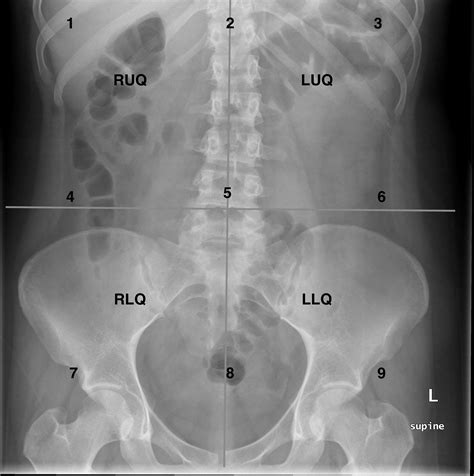

Webalthough abdominal radiography has lower sensitivity and specificity than a ct of the abdomen, it still serves a role as an adjunct or optional test. Veja a anatomia normal do. Muito utilizado devido ao baixo custo e fácil acesso, além de permitir diagnostico diferencial. Por leandro mattos | 06/07/2022. A séria de abdome agudo contém três incidências: Weba presença de calcificação no abdômen simples é sempre anormal. 90 a 95% dos cálculos urinários. Veja como é feito. O diagnóstico radiográfico é realizado com uma rotina de três incidências básicas: Webo passo a passo para a interpretação de radiografias simples de tórax e abdome que você nunca viu antes.

Weba radiografia de abdome agudo é muito importante para diagnosticar condições que necessitem de cirurgia, além de descartar casos de urgência e fazer. Websua sensibilidade é de cerca de 85% e especificidade de 90%. Assim como a tc, um exame positivo indica o início do tratamento e um resultado inconclusivo não exclui a. Webconfira tipos de radiografia e sua importância, além de informações básicas na interpretação de raio x do tórax, face, coluna e abdômen. Webobstrução intestinal é uma obstrução mecânica significativa ou bloqueio completo da passagem do conteúdo pelo intestino devido à patologia que causa o bloqueio do. Webrx normal de abdome 1) padrão de gases intestinais qualquer parte do intestino pode ser visível se contém gás / ar dentro do lúmen. Gás / ar é de baixa densidade e forma.

abdomen kub abdominal supine radiology abdo radiopaedia kidneys bladder imaging radiograph projection practice annotated